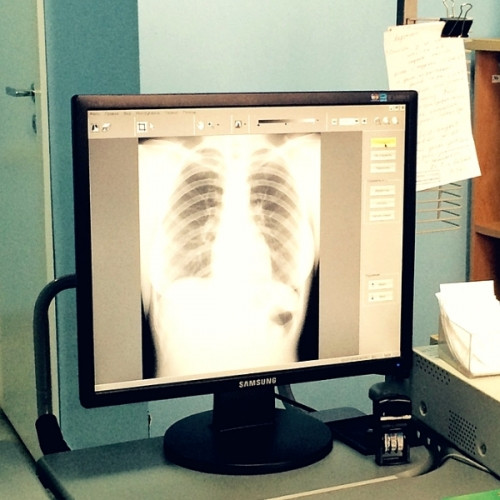

Проверяйте здоровье бесплатно. Завтра, 17 ноября, в поликлинике №1 второй горбольницы вас ждут на диспансерные обследования

Поликлиника на Уральской приглашает на диспансеризацию каждый рабочий день и в диспансерные субботы.

Зачем мне диспансеризация?

Обследования покажут:

- насколько вы здоровы сейчас;

- к каким заболеваниям вы предрасположены;

- что нужно сделать, чтобы сохранить здоровье и прожить долго и счастливо.

А если нет жалоб на здоровье?

Мы не всегда чувствуем неполадки в организме. Можем не знать, что у нас высокое внутриглазное давление, не чувствовать изменений в работе сердца. Не каждый поймет, что у него повышенное артериальное давление, потому что голова может не болеть.

Ежегодно именно диспансеризация ещё в «дожалобный» период выявляет ряд серьёзнейших заболеваний. Как известно, раннее обнаружение болезни увеличивает эффективность лечения, позволяет сохранить качество и продолжительность жизни.

Как выглядит диспансеризация?

Она состоит из двух этапов. Первый определяет признаки хронических неинфекционных заболеваний и риски их развития. Если обнаружится заболевание или склонность к нему, вас переведут на второй этап, более углубленные обследования.